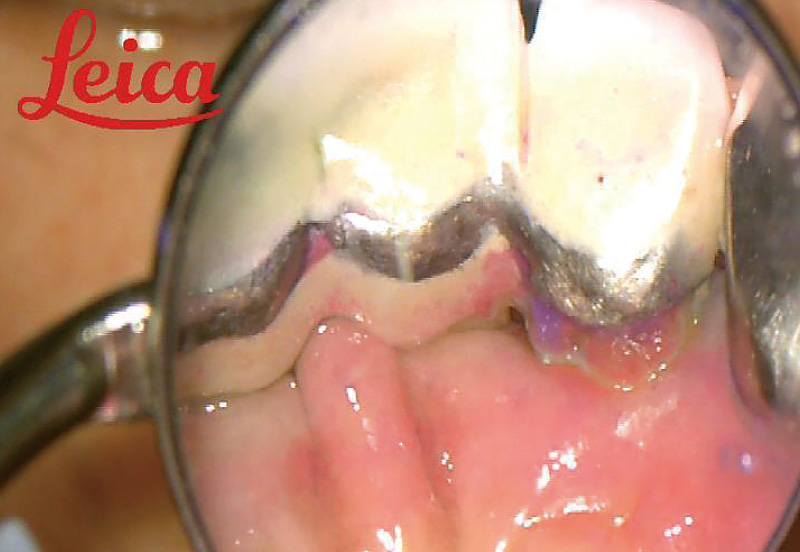

![[写真] マイクロスコープ拡大視野下で染まった部位を確認](/academic/dentalmagazine/wp-content/uploads/sites/2/2023/12/187-13_photo07.jpg)

症例1-4 マイクロスコープ拡大視野下で染まった部位を確認。 -

![[写真] 微細な部位に付着しているプラーク](/academic/dentalmagazine/wp-content/uploads/sites/2/2023/12/187-13_photo08.jpg)

症例1-5 微細な部位に付着しているプラークまで徹底除去。 -